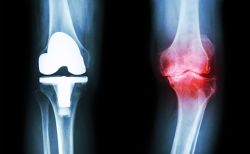

Nếu như trước đây, thoái hóa khớp chưa biện pháp điều trị dứt điểm cho tình trạng đau, viêm thì gần đây, ứng dụng liệu pháp PRP – huyết tương giàu tiểu cầu đã mang đến tin vui cho các bệnh nhân. Không chỉ KIỂM SOÁT CƠN ĐAU, triệu chứng, PHỤC HỒI chức năng vận động cho người bệnh mà còn hiệu quả cả về mặt TÁI TẠO, phục hồi sụn khớp. Đây là ưu điểm mả các phương pháp nội khoa khác không thể làm được.

TIÊM PRP – BƯỚC TIẾN MỚI TRONG ĐIỀU TRỊ THOÁI HÓA KHỚP![]()

PRP lấy từ chính máu của bệnh nhân với hàm lượng tiểu cầu cao gấp 5-7 lần so với P.R.P từ máu thông thường, khi được đưa vào vùng điều trị sẽ giải phóng nhiều yếu tố tăng trưởng. Chính những yếu tố này giúp thúc đẩy quá trình tái tạo, phục hồi mô tế bào bị viêm, tổn thương theo cơ chế tự nhiên một cách nhanh chóng cùng nhiều ưu điểm vượt trội:

.Đặc biệt, tiêm PRP đã được Hội khớp học Hoa Kỳ chứng minh lâm sàng là phương pháp an toàn, hiệu quả trong điều trị thoái hoá khớp gối. Hiện nay, liệu pháp này đang được ứng dụng rộng rãi tại Bệnh viện đa khoa Phương Đông cùng cam kết hiệu quả tối ưu ngay sau điều trị.